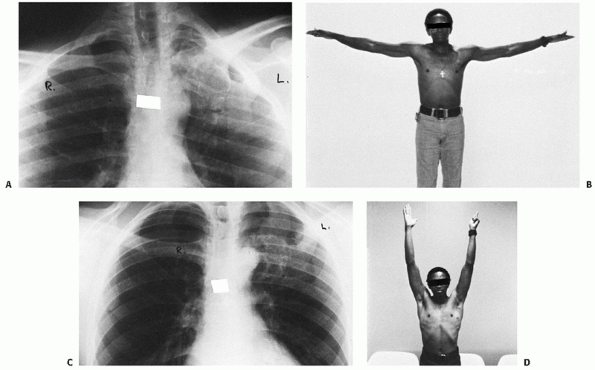

FIGURE 40-20 Posterior dislocation of the right SC joint. A.

A 16-year-old boy has a 48-hour-old posterior dislocation of the right medial clavicle that occurred from a direct blow to the anterior right clavicle. He noted immediate onset of difficulty in swallowing and some hoarseness in his voice. B. A 40-degree cephalic tilt radiograph confirmed the posterior displacement of the right medial clavicle as compared with the left clavicle. Because of the patient’s age, this was considered most likely to be a physeal injury of the right medial clavicle. C. Because the injury was 48 hours old, we were unable to reduce the dislocation with simple traction on the arm. The right shoulder was surgically cleansed so that a sterile towel clip could be used. D. With the towel clip placed securely around the clavicle and with continued lateral traction, a visible and audible reduction occurred. E. Postreduction radiographs showed that the medial clavicle had been restored to its normal position. The reduction was quite stable, and the patient’s shoulders were held back with a figure-of-eight strap. F. The right clavicle has remained reduced. Note the periosteal new bone formation along the superior and inferior borders of the right clavicle. This is the result of a physeal injury, whereby the epiphysis remains adjacent to the manubrium while the clavicle is displaced out of a split in the periosteal tube. |